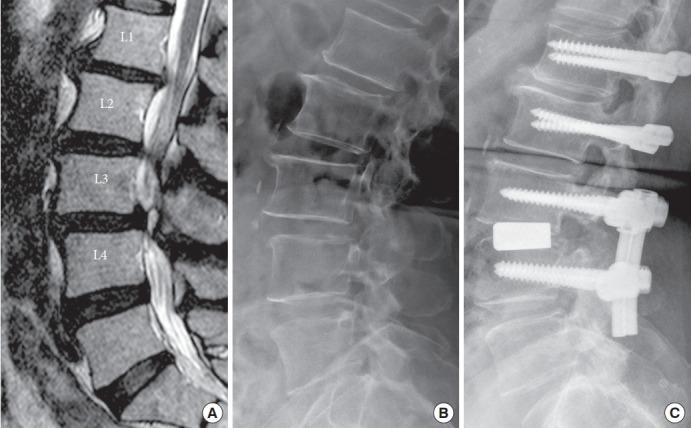

This retrospective study included 35 consecutive patients with multilevel lumbar degeneration with or without spondylolisthesis who underwent surgery using the DTO system. Imaging studies included pre- and postoperative radiography, magnetic resonance imaging, and computed tomography. The clinical outcomes were measured by Japanese Orthopedic Association (JOA) scores, Oswestry Disability Index (ODI) scores, and a visual analogue scale (VAS) for back and leg pain.

Thirty patients (85.7%) with a mean age of 61.9 years completed the follow-up, with a mean duration of 35.1 months. There were 21 patients in the spondylolisthesis group and 9 in the stenosis group. The spondylolisthesis group had worse functional scores than the stenosis group preoperatively. After DTO surgery, all patients showed significant improvements in clinical outcomes, including VAS for back and leg pain, ODI, and JOA scores (p < 0.05). There were no significant differences in clinical outcomes between the 2 groups. At a 2-year follow-up, lumbar alignment was well maintained in both groups (p = 0.116). There were no significant differences in lumbar alignment between the 2 groups.